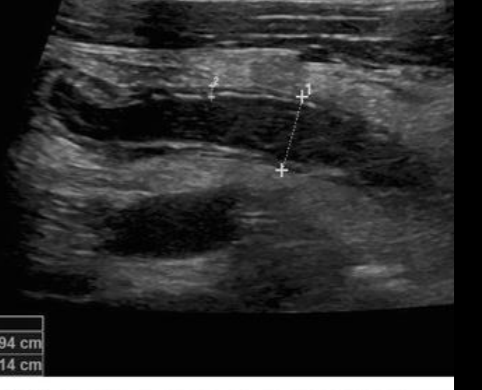

Apendice distendido en mm

A

> 7mm

Pared apendice ??

> 3mm

de lado US